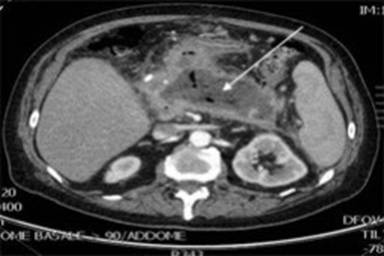

Three months later the patient was admitted to our Department with anorexia and repeated episodes of vomiting. A contrast-enhanced abdominal CT scan showed a voluminous pancreatic pseudocyst [1] occluding the stomach lumen and a pylethrombosis (Figure 1).

Figure 1. Voluminous pseudocyst (arrow) compressing the stomach, associated to splenic vein thrombosis |